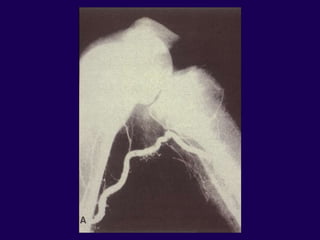

Supracondylar Fractures

After TKR

l Notching of the femoral cortex

l Osteoporosis

l Prolonged steroid use

l Preexisting neurologic

disorders

OSTEOPOROSIS

Bogoch, et al, CORR 1986